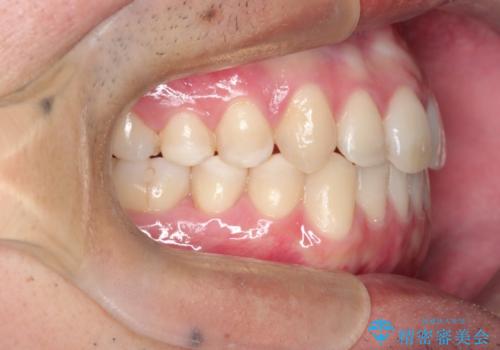

【MSE+インビザライン】前歯のガタガタ

上の歯のアーチが狭窄していたため、骨の幅を広くするためにMSE(急速拡大装置)を使用してからインビザライン にて治療を行いました。

MSE(急速拡大装置)を用いたことで、短期間で奥歯の噛み合わせもしっかりと治すことができました。